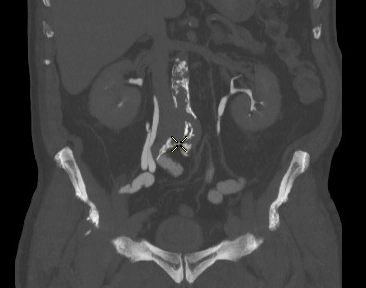

Sa lồi niệu quản (Ureterocele)